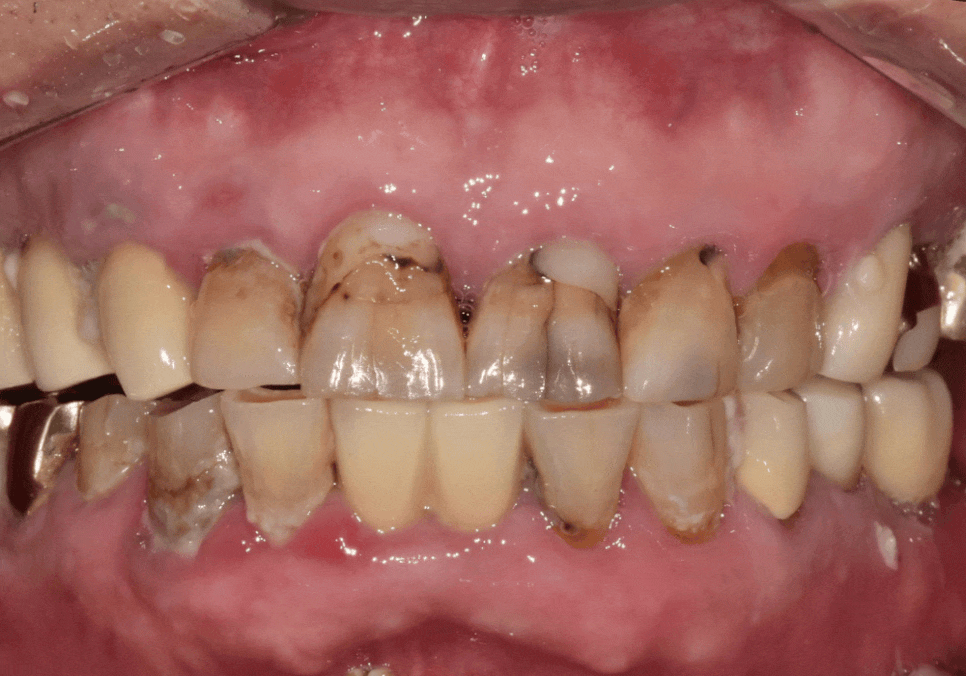

최근 내원하신 환자분은

앞니 사이 음식물 끼임이 심해지면서

치아가 검게 변색된 상태였어요.

240223

육안으로도 깊은 충치가 보였고,

과거에 레진으로 치료했던 부위 안쪽으로

2차 충치가 진행되고 있었죠.

위의 앞니에 금도 가있네요.

방사선 사진을 살펴보니,

충치가 신경까지 아주 가깝게

진행되어 있었는데요...

이번에 문제가 생긴 앞니들은

신경치료 후 보철물을 연결하는

스플린트 형태로 제작하기로 계획했습니다.

치료 계획

#12~23 신경치료 및 지르코니아 스플린트

#42, 43, 44 및 #32, 33 신경치료

및 지르코니아 스플린트

3)진행 방식

연세를 고려하여 상악부터 순차적으로 천천히 진행